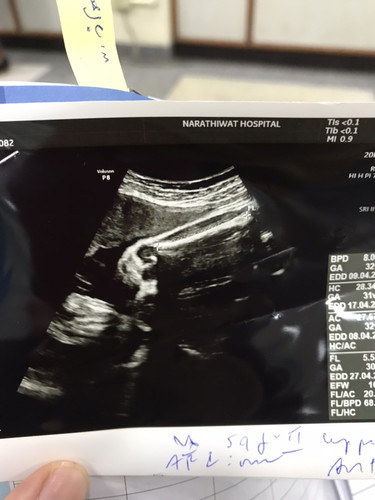

คือส่วนไหนของลูกค่ะ

ขาค่ะ